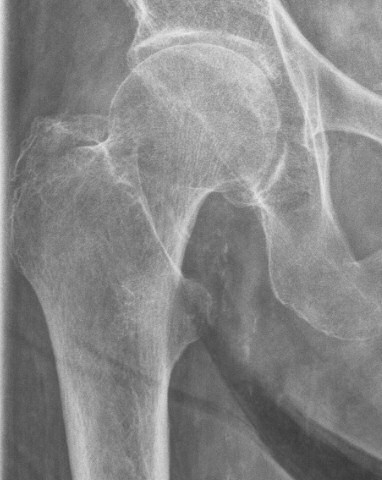

Trokanter majorfraktur, behandlades med direkt mobilisering